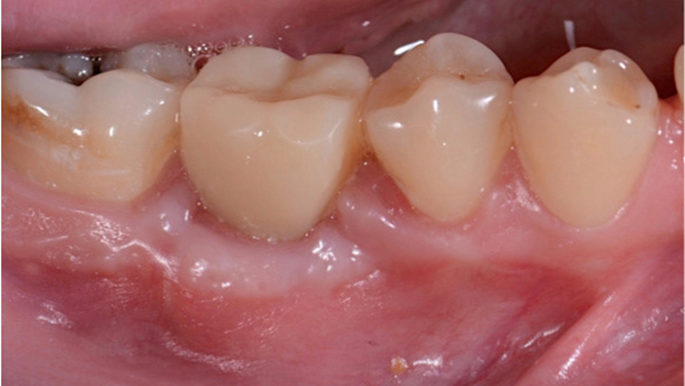

Clinical case: Delayed implant placement: sinus floor elevation by means of lateral

approach & implant placement with GBR

- Courtesy of Dr. Irfan Abas, Netherlands -

Clinical case: # 46 implant placement & GBR using i-Gen membrane for significant vertical resorption & mixed bone defect

- Courtesy of Dr. Iulian Filipov, Romania -